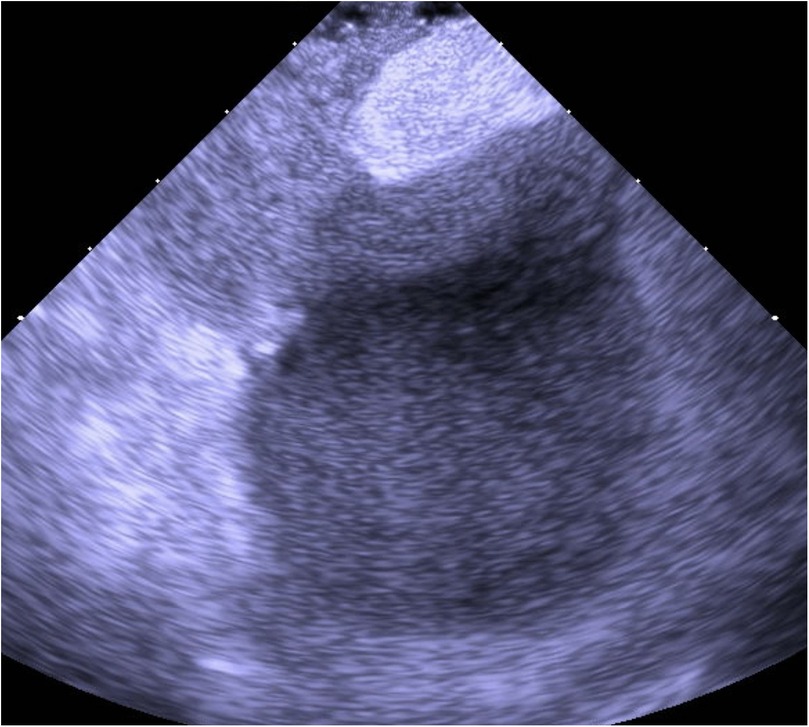

An 80-year-old man presented with progressive dyspnea and severe hypoxemia refractory to high-flow oxygen therapy, ultimately found to have a large persistent patent foramen ovale (PFO) mediated right-to-left-shunt (RTLS). The patient underwent successful percutaneous PFO closure via a 35 mm Amplatz septal occluder guided by intracardiac echocardiography (ICE), resulting in complete resolution of the patient's hypoxia within 24 hours. This case highlights the workup of systemic refractory hypoxemia, the importance of cardiac shunt physiology in considering a RTLS, and the utility of PFO closure under ICE-guidance. For patients with a PFO-mediated RTLS, percutaneous closure offers an effective therapeutic option.